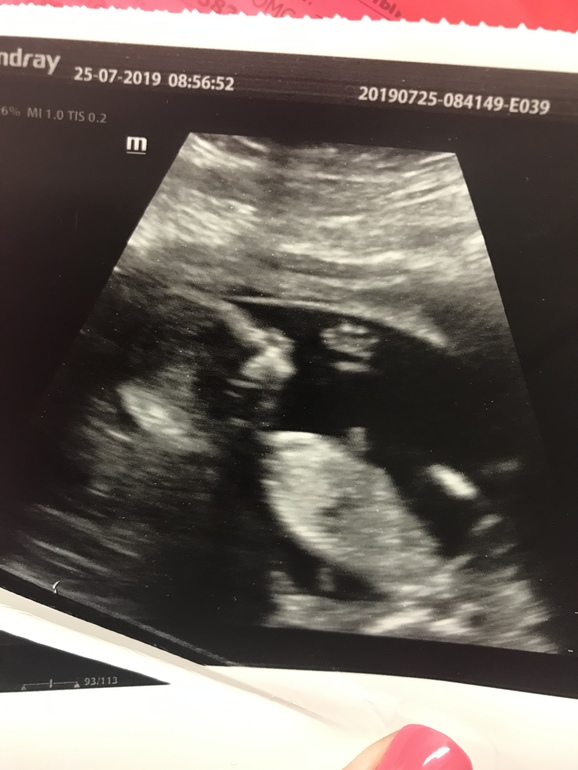

Ну вот и стали наши шевелюшки четкими))) особенно во время завтрака, или днём когда кушаю сладости. Сходили на узи пол посмотреть и фоточку сделать (под кат) доктор на узи дал нам результат с точность 70% что у нас доченька ( почему такой процент не понятно🤔) точнее узнаем на втором скрининге)) конечно мальчика мне хотелось бы, потому старшая дочурка, но муж все равно рад, только с именем мы определиться никак не можем (( может ещё не время?! Ну и фоточки, наши 15 неделек 5 дней и фото с узи, Доченька машет нам ручкой))